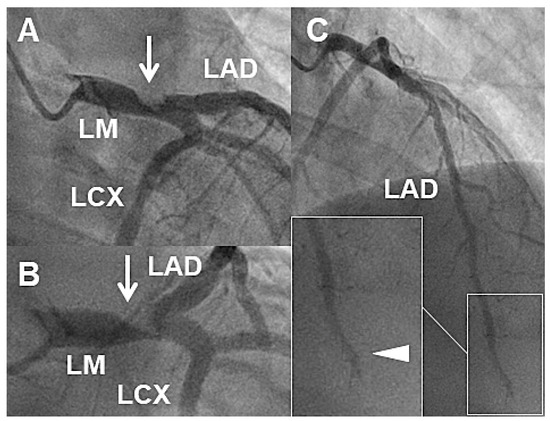

Acute myocardial infarction (AMI) in endurance athletes such as triathletes is rare but not impossible. However, the assessment of endurance athlete with possible AMI is very challenging because application of the classical diagnostic tools, i.e., history, electrocardiogram and cardiac troponin testing is different [...] Read more.

Acute myocardial infarction (AMI) in endurance athletes such as triathletes is rare but not impossible. However, the assessment of endurance athlete with possible AMI is very challenging because application of the classical diagnostic tools, i.e., history, electrocardiogram and cardiac troponin testing is different from their use in “normal” AMI patients and requires specific knowledge regarding the cardiovascular phenotype of the endurance athlete in general and during a competitive event. To illustrate this, we report on three different subjects referred with similar presentations but very different underlying problems on a single day during one single triathlon event. Full article

Show Figures

Figure 1